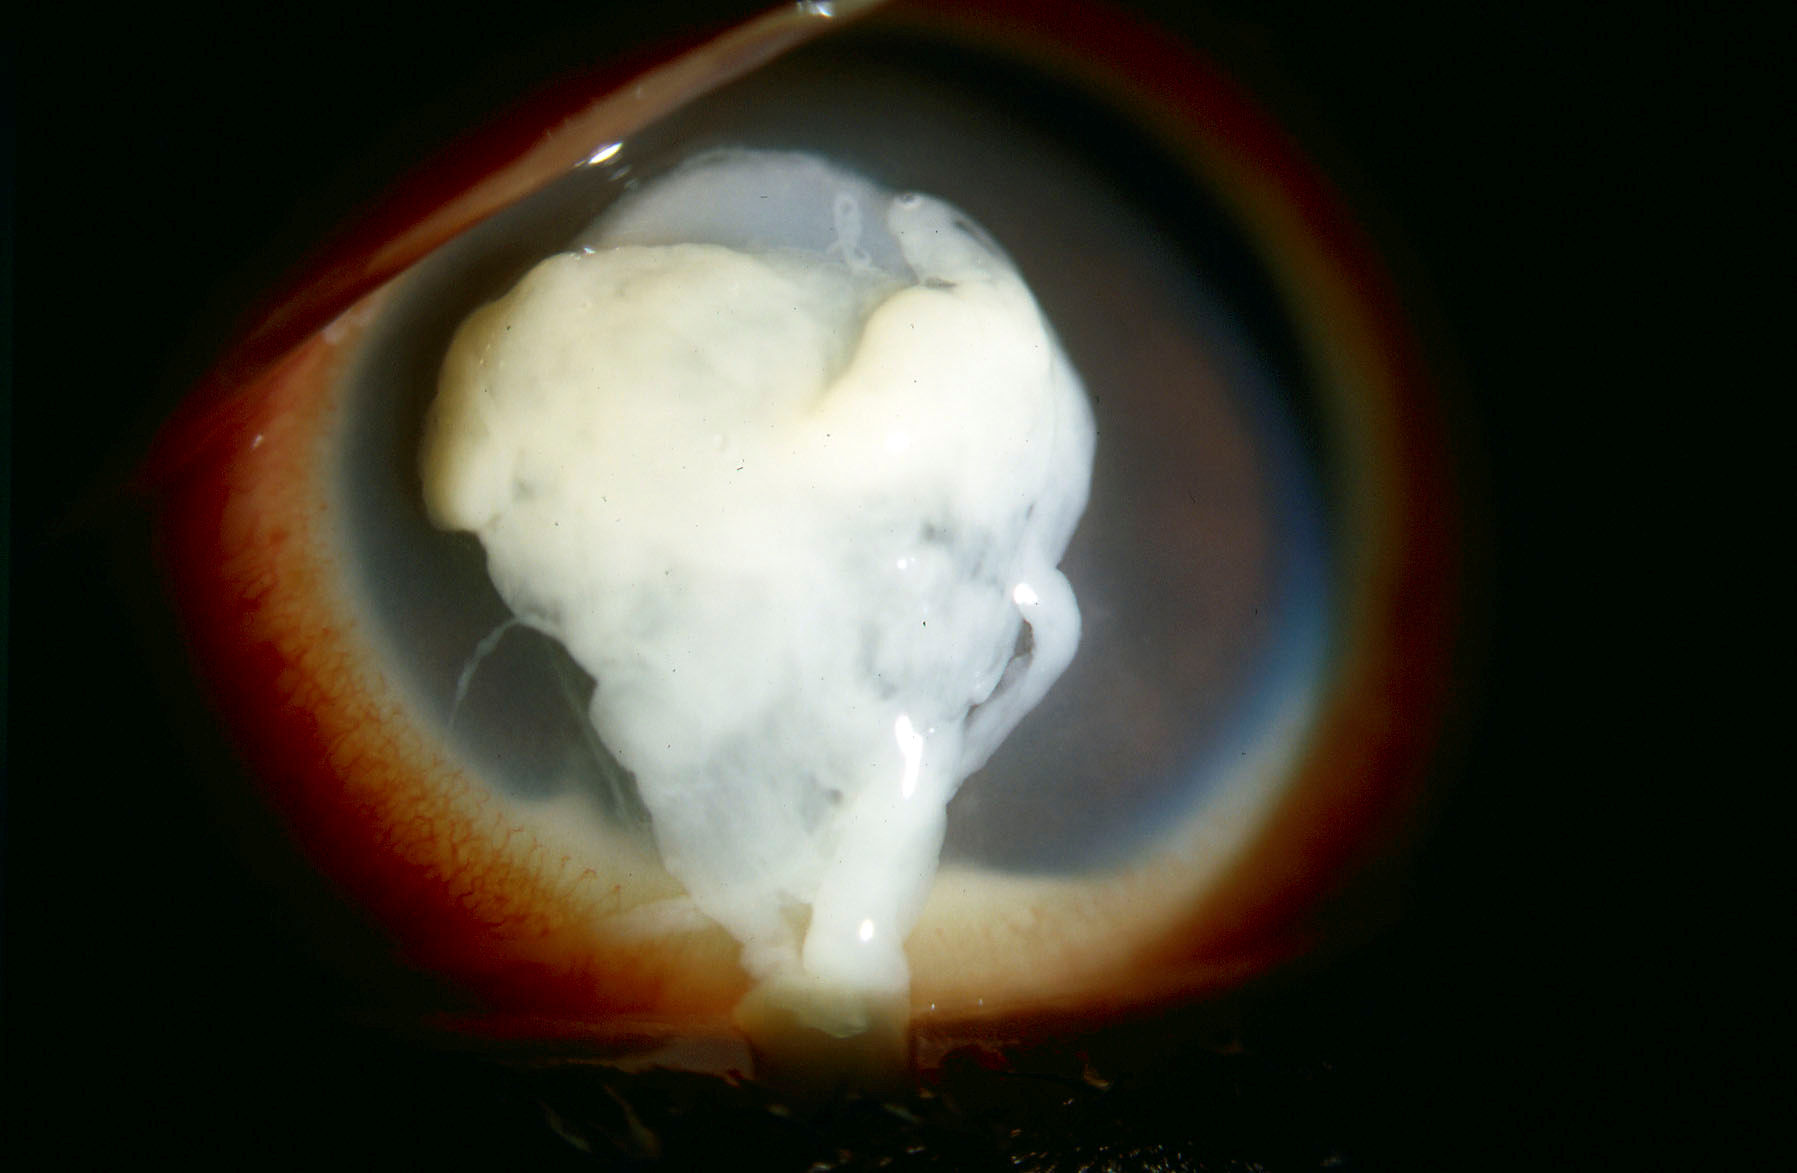

Ill-fitting lenses can cause eye pain, bacterial infections, and corneal ulcers. One study found that wearing decorative lenses increased the risk for developing keratitis, a potentially blinding infection that causes an ulcer in the eye. This increased risk was over 16 times more likely than those seen in vision correcting (“regular”) lenses.

“I’ve seen many young patients who were not aware of the dangers of these products and are now living with permanent vision loss,” said Thomas L. Steinemann, MD, Professor of Ophthalmology at Case Western Reserve University/MetroHealth Medical Center and a Prevent Blindness volunteer. “Parents should be on the alert to protect their children’s vision by assuring that their contact lenses are worn only under the supervision of an eye doctor.”

Serious eye injuries caused by illegally sold cosmetic contact lenses: Photo 1Photo 2 (Photo credit: Dr. Thomas L. Steinemann)